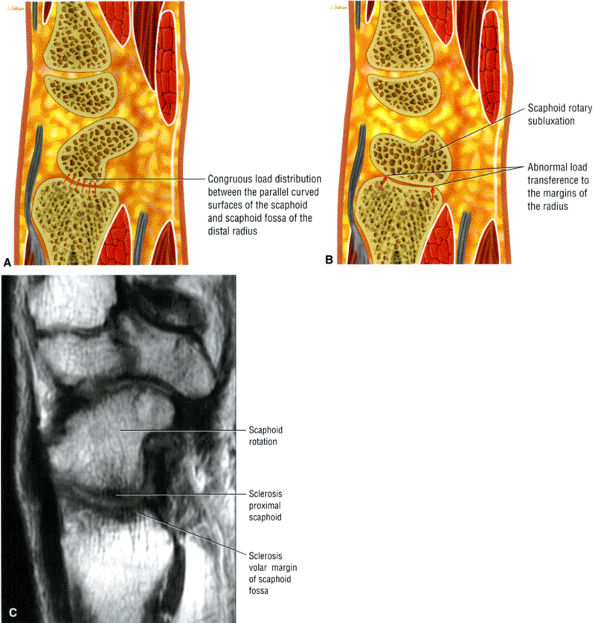

At the site of the radiolunate articulation, the distal articular surfaces of the radius and ulna are usually at the same level (i.e., neutral ulnar variance). Alternatively, the ulna may be relatively long (positive ulnar variance), leading to an ulnar abutment syndrome, or relatively short (negative ulnar variance), as is often seen in Kienböck's disease. The distal radius forms two facets that articulate with the scaphoid and lunate of the proximal carpal row. This articulation of the proximal pole of the scaphoid in the scaphoid fossa is quite congruent, and even a small degree of malrotation of the scaphoid may cause incongruent loading of the articular cartilage and subsequent degeneration (such as that which accompanies a SLAC wrist, as described by Watson and Ryu37). The lunate facet commonly becomes incongruent following distal radius fractures, especially die-punch-type fractures. The interosseous ligaments join the proximal carpal bones at their proximal edges.36